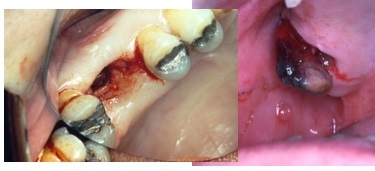

aetiology of OAC/OAF

Extraction of toot/RR and due to close relation of floor maxillary antrum/sinus and tooth create a communication either by breaking bone of floor or ripping the mucosa lining and oral cavity(previously wasn’t there)

* Get bacteria ingress into sinus

* Affect function of sinus

OAC is

acute

just happened, immediate post extraction - can see bleeding, potential prolapse of lining of maxillary antrum

OAF is

chronic

communication made - management failed and opening persists - sinus tract has been created now

no bleeding